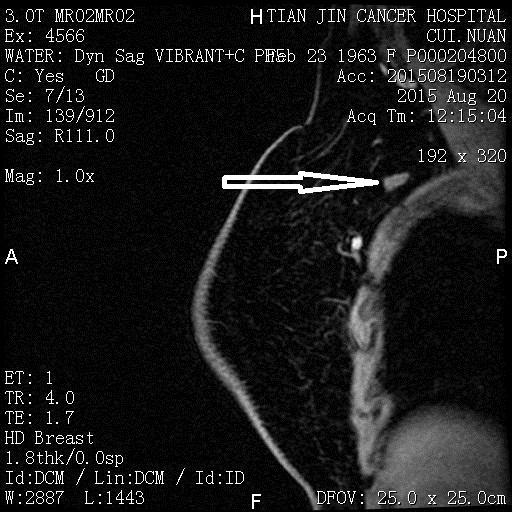

新辅助化疗前MRI

*箭头所指为内乳区转移淋巴结

*箭头所指为乳腺原发肿瘤

*箭头所指为腋窝转移淋巴结